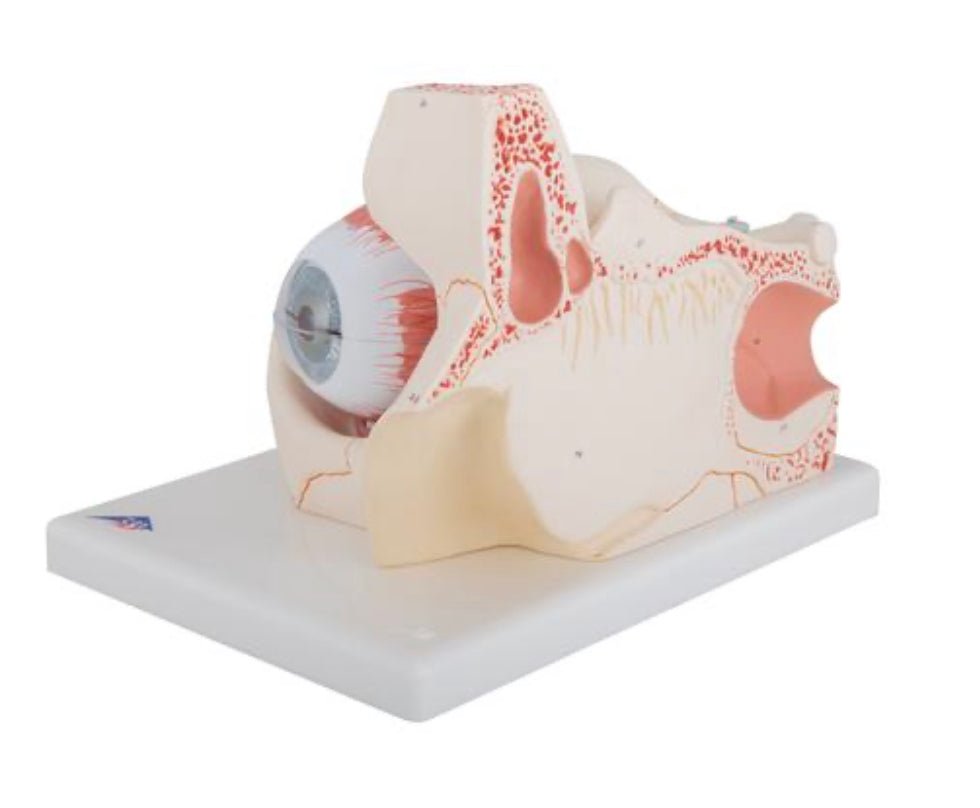

Anatomical models

Selling anatomical models is the mainstay of eAnatomi, although we also spend a lot of resources developing our own anatomical materials such as posters. Anatomical models are used for various purposes and can show both defined tissues, organs and organ systems. Are you looking for a simple model of bone tissue or perhaps an advanced torso model based on MRI technology, you can find it all at eanatomi.com.